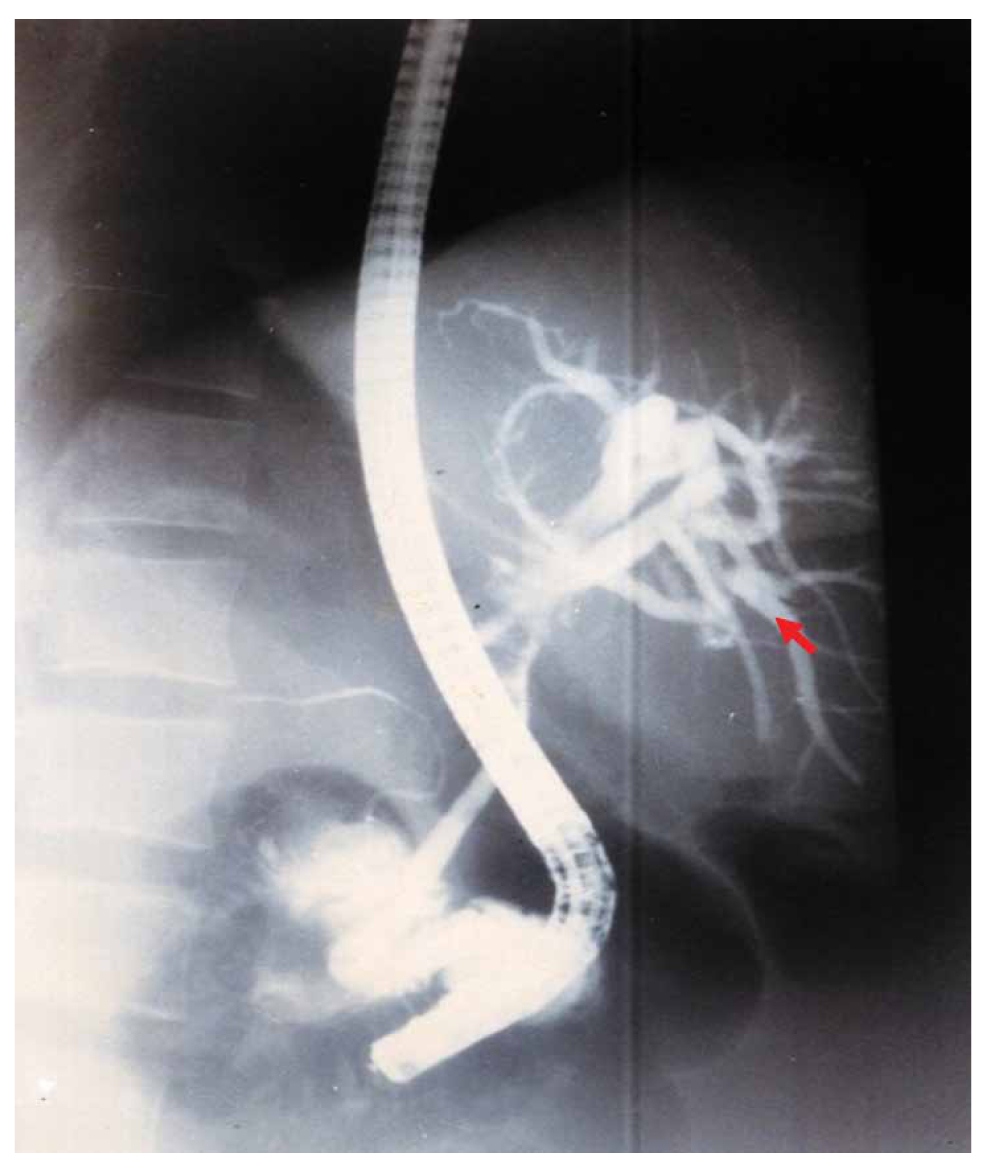

Three patients developed CSC at 2, 3, and 7 months postoperatively (Table 1). The diagnosis was established based on the following criteria: (i) a history of previous surgery for LHC with documented intracystic injection of scolicidal agents; (ii) early postoperative onset of progressive obstructive jaundice; (iii) normal biliary tract appearance during the initial surgery and on intraoperative cholangiography (IOC), excluding preexisting bile duct narrowing; (iv) cholangiographic evidence (ERCP or percutaneous cholangiography) of new multifocal or segmental biliary strictures consistent with sclerosing cholangitis (Figure 1); and (v) exclusion of other potential causes such as iatrogenic bile duct injury (no intraoperative injury identified), primary sclerosing cholangitis (PSC) (no diffuse inflammatory involvement or extrahepatic association), and neoplastic strictures (no mass lesion on imaging or histology). These criteria are consistent with those described by Belghiti et al. and subsequent reports.

Figure 1. Endoscopic retrograde cholangiopancreatography (ERCP) showing stenosis of the bile duct convergence (arrow).

Symptoms of CSC are similar to those of PSC and manifest as progressive jaundice, which is often confused with iatrogenic biliary trauma and biliary obstruction caused by scolex fragments, with a rapidly increasing GGT level within seven days, followed by a progressive increase in BT and PAL levels. Ultrasound (US), computed tomography (CT), or endoscopic US may show suggestive anomalies and allow the exclusion of other causes of cholestatic jaundice. However, the normality of these examinations does not exclude the diagnosis of CSC. The reference examination is direct bile duct opacification, by transhepatic puncture or preferably by ERCP. Anatomically, several patterns of lesions have been described in CSC. One common feature is the alternation of stenotic and dilated zones, producing a characteristic mound-like appearance. In other cases, diffuse segmental stenoses are observed, or alternating stenoses with non-stenotic peripheral segments. The involvement of peripheral bile ducts may result in a marked reduction of bile tree branching, creating the so-called “dead tree” appearance. In addition, a stenotic narrowing at the level of the main bile duct can be associated with sacculated or ampullary dilatation of the proximal intrahepatic bile ducts.